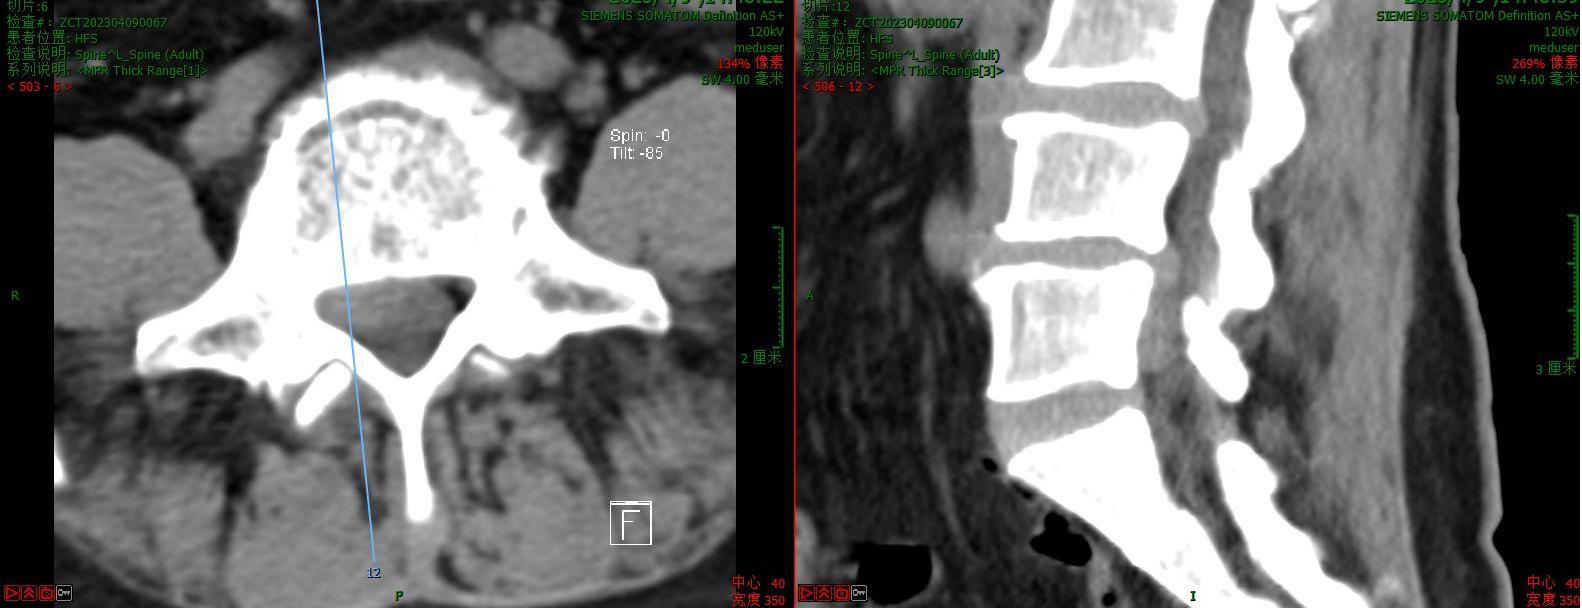

第一例病例为一名中年男性,腰4/5椎间盘突脱出并向下游离接近腰5/骶1椎间隙,为其实施VBE内镜下突出髓核单纯摘除术。患者术前腰痛伴右下肢疼痛麻木1个月余,右拇指背伸肌力明显下降。术后疼痛完全缓解,肌力较前部分恢复,有轻度麻木。

术前CT

术前核磁